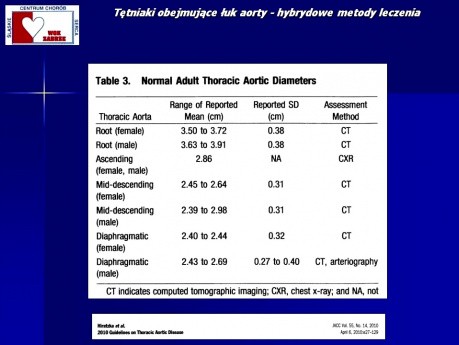

Tętniaki obejmujące łuk aorty - hybrydowe metody...

Prezentacja na temat hybrydowych metod leczenia tętniaków obejmujących łuk aorty. Wykład prowadzi dr n. med. Roman Przybylski - zastępca Ordynatora Oddziału Klinicznego Kardiochirurgii i Transplantologii...